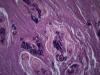

Опухоль матки |

Плоскоклеточный умереннодифференцированный рак,инвазия в железы.